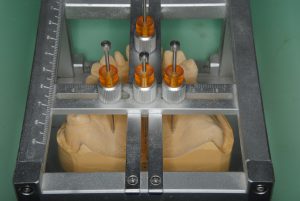

3月9日、10日、今年もこのセミナーが始まりました。私はインストラクターとなっていますが、奥が深い世界で、まだまだ学ぶことの方が教えることより多い感じです。御年83歳になられる阿部先生ですが、例年通り講義、デモを行っています。何十年にも渡って口だけでなく、手で技術を受講生の前で披露するセミナーは他に聞いたことがありません。各ステップがあるので患者さんも毎月決まった時間に来なければなりません。トラブルなく毎年ゴールまで導くさまは年を重ねるごとに、すごいことだなと思います。有歯顎で総合治療を行う際にも咬合をどう仕上げるかは基準がなければ勘だけでやらざるを得なくなります。今年は新受講生が多く、再受講生とあわせて会場がいっぱいでした。再受講生組にはプレゼンさせていただきました。今年も大いに盛り上がり、学べそうです。